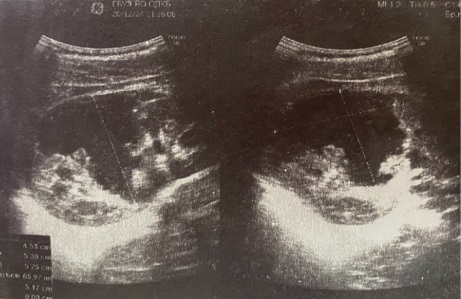

В пяти случаях из семи — 71,4 % — хирургическая находка соответствовала результатам ультразвукового исследования, что подтверждается следующими клиническими иллюстрациями (рис. 2, рис. 3).

Рис. 2. А. Неоднородность нижнего полюса яичка и придатка (УЗИ в горизонтальном срезе)

Рис. 2. Б. Отрыв хвоста придатка в области нижнего полюса яичка

Рис. 2. Больной М, 15 лет. 12 часов после травмы — удар ногой в промежность снизу верх